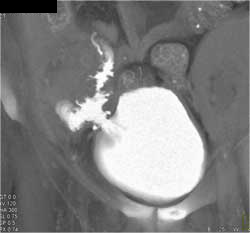

Diagnosis

Normal CT Urogram